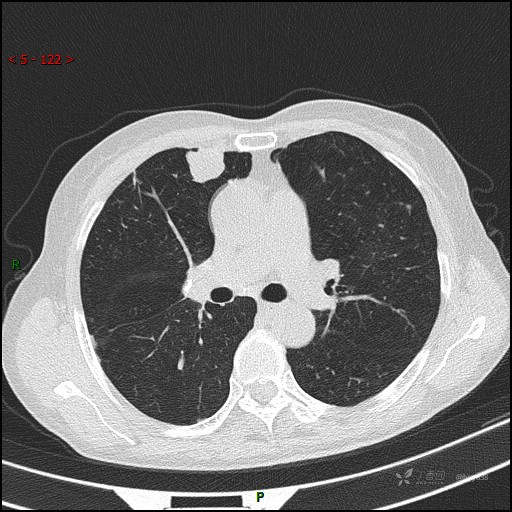

辅助检查:CT

讨论:病变性质?

增强动脉期

静脉期